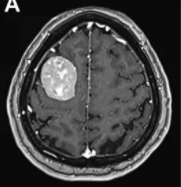

近些年来中枢神经系统肿瘤发病率不断升高,而脑膜瘤是中枢神经系统常见的原发性肿瘤,占颅内肿瘤的13%-26%。脑膜瘤高发于女性,主要集中在中老年群体。脑膜路由肿瘤性脑膜上皮细...

53岁的李阿姨一直有慢性头痛的病史,刚开始一家人都以为这只是个头疼脑热的小毛病,直到有一天,李阿姨因突发癫痫送医,结果被查出大脑左额凸面及前段大脑镰旁有肿瘤占位,于...